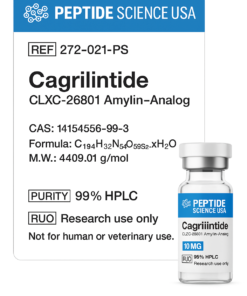

Related products

Peptides

Peptides

Peptides

Peptides

Peptides

Peptides

Peptides

Peptide